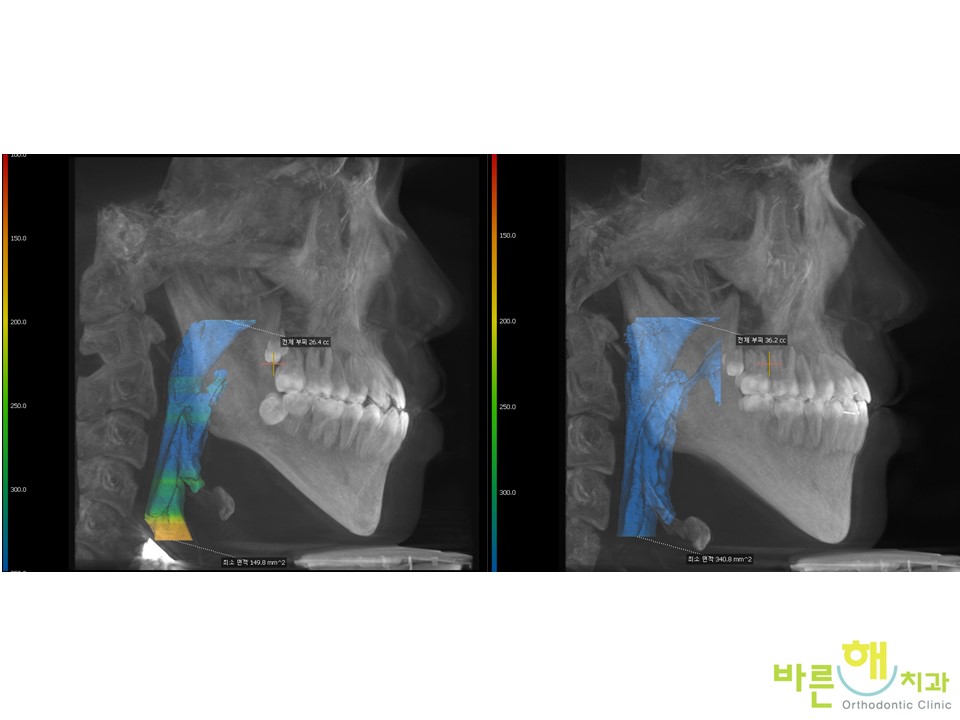

ºñ¼ö¼ú ÁÖ°ÆÅÎ ±³Á¤Ä¡·á ÈÄ¿¡

ÇôÀÇ À§Ä¡³ª ¿îµ¿¼ºÀÌ °³¼±µÈ °ÍÀ¸·Î

±âµµµµ ³Ð¾îÁø °ÍÀ» º¼ ¼ö ÀÖ½À´Ï´Ù.